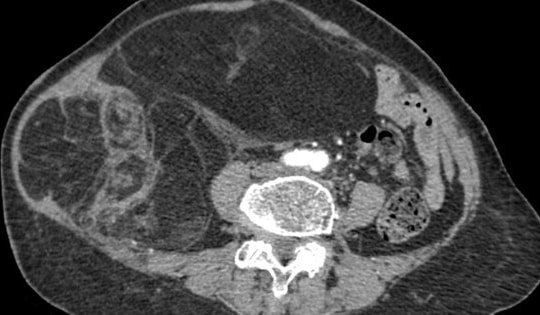

Cùng lúc nhiễm nhiều loại giun sán, gan của cụ bà chứa toàn mủ đục